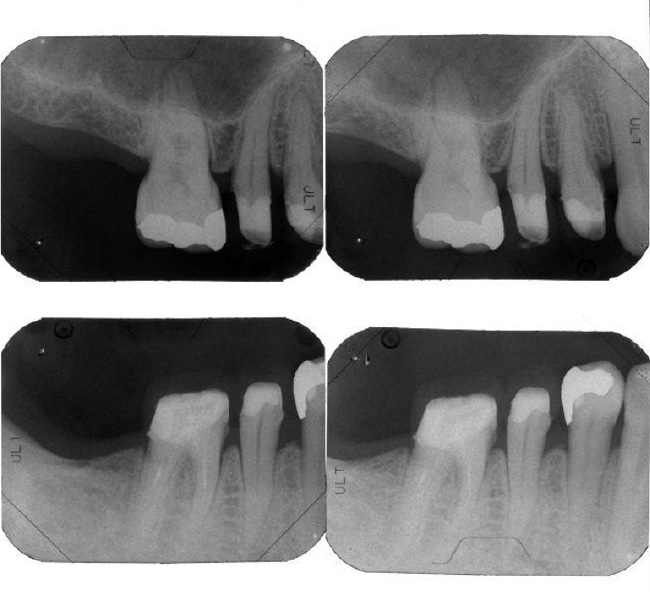

治療前

| 主訴 | 数年前から左下の一番奥の歯が噛んだときに痛む。 通院していた歯科で痛みはとれないがまだ抜かない方が良いといわれたが、ずっと痛いままなので不安になり来院。 |

| 治療内容 | 全顎治療:歯周病治療、抜歯、根管治療、 咬合治療・矯正治療、フルメタルクラウン(保険) |